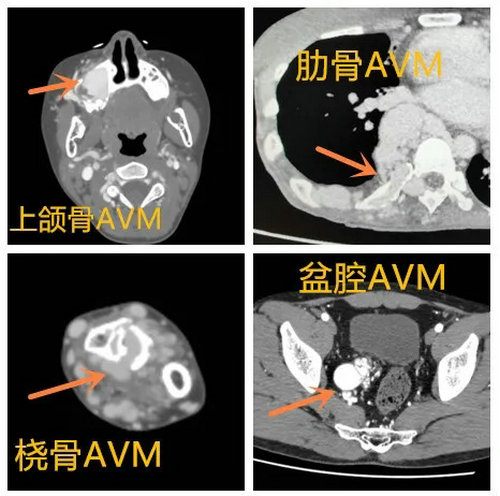

动静脉畸形的辅助检查包括超声、CT、磁共振、动脉造影等技术。目前来说,增强CT(图5)及DSA(图6)可明确病变累及的部位大小、范围,是确定诊断及治疗的重要方法。特别是对外观不易发现检查出的骨及盆腔动脉静脉畸形(图7),能避免误诊及漏诊。

▲ 骨及盆腔AVM(图7)